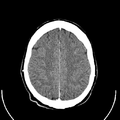

أشعة مقطعية للرأس توضح صورة المخ